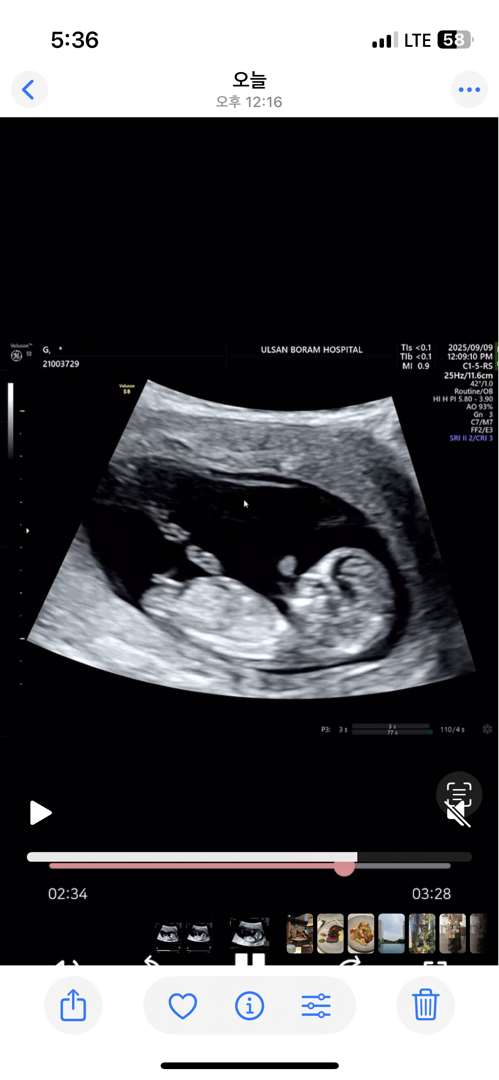

12주1일차에요 각도법으로 알 수 있을까요 ㅎㅎㅎ!

각도법 봐주세용🥹